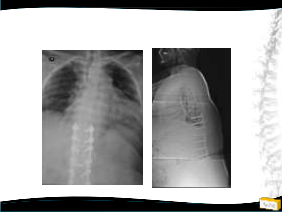

• 48y, K

• Pilates

Öğretmeni

• Şiddetli bel ağrısı

Tedavi ?

– Konservatif

– Cerrahi

• Teknik?

Yapılan Ameliyat

• T12-L5 tp fiksasyon

• L4 laminektomi ile L3-L4 ve L4-L5 mesafelerinin dekompresyonu

• Posterolateral grefleme

• 3 yıllık takipte sorunsuz